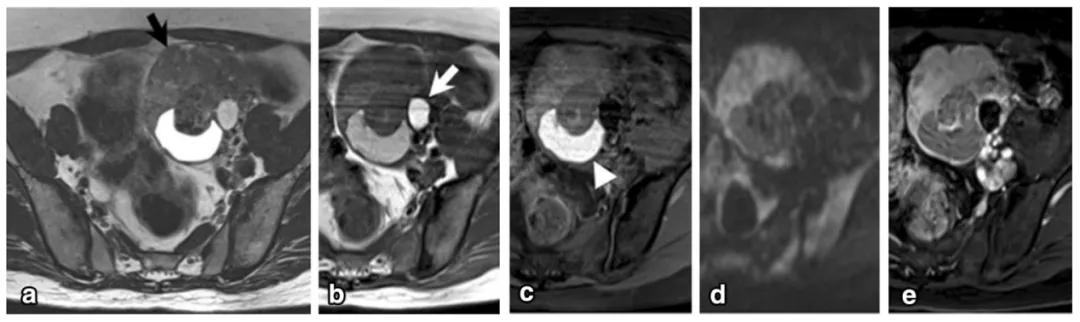

女,47 岁,卵巢子宫内膜样癌。右侧卵巢异常信号肿物,T2WI 混杂稍高及高信号(图 a),DWI 高信号(图 b),增强扫描不均匀强化(图 c)。肿物内见条片状裂隙样异常信号(箭头),T2WI 呈高信号、DWI 低信号、增强扫描未见强化。

女,64 岁,雌激素升高,卵巢子宫内膜样癌。卵巢肿物由三部分构成,偏右侧是囊性成分;中间部分(箭头)T2WI 及 DWI 呈低信号(a 及 b),增强扫描明显强化(c 增强早期,d 增强晚期);偏左侧部分 T2WI 稍高信号,DWI 高信号,增强扫描明显强化。HE 染色显示中间部分肿物由功能性纤维间质构成(图 e)。HE 染色肿瘤左侧部分显示子宫内膜样癌与性索间质肿瘤类似。矢状位显示子宫体积增大(图 g)

女,50 岁,卵巢类癌与成熟畸胎瘤及卵巢甲状腺肿。左卵巢囊实性肿物,实性成分 T2WI 呈低信号(图 a 黑箭),T1WI 呈稍低信号(图 b),T1WI 压脂呈稍高信号(图 c),DWI 呈高信号(图 d),增强扫描明显强化(图 e)。肿物内囊性成分 T1WI 呈高信号(白箭头)。肿物并存成熟畸胎瘤(白箭)